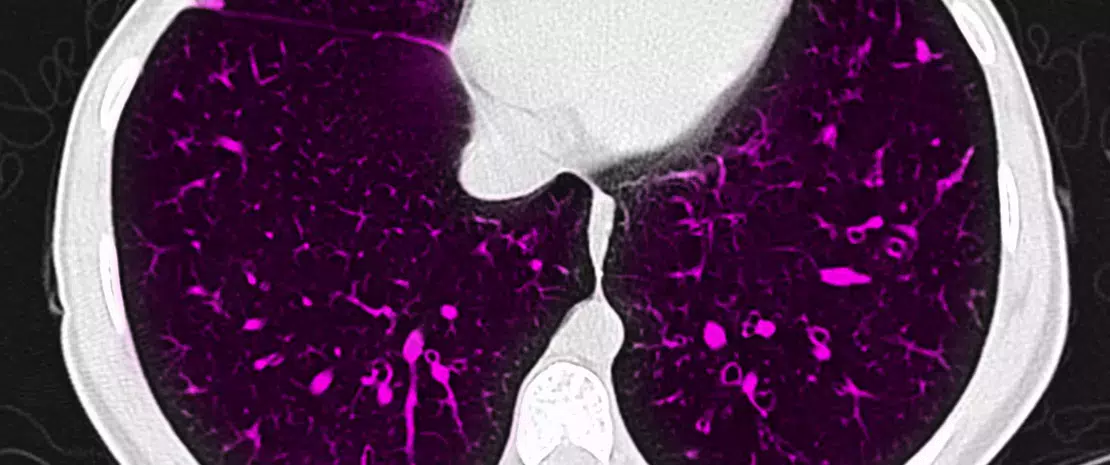

Cystic fibrosis (CF) is a progressive, genetic disease that causes persistent lower respiratory infections and is related to different systemic symptoms and signs. More than 70,000 people live with CF worldwide [1].

The types and severity of symptoms can differ widely from person to person and are mainly related to the age of the patient as well as age at diagnosis. Children and adolescents with CF have a wide range of symptoms and signs including gastrointestinal manifestations. Recent studies have shown that dysbiosis is a feature of CF, leading to reports focusing on the relationship between the composition of the airway microbiota and clinical features and pulmonary function in patients with CF [2].